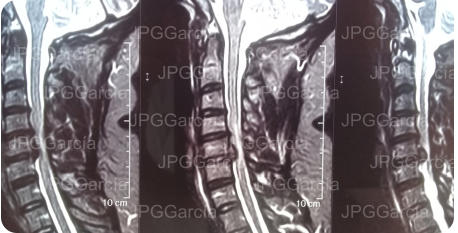

Tratamiento microquirúrgico de hernia extruida cervical con mielopatía

Estudios de control postquirúrgico radiográfico y de resonancia magnética